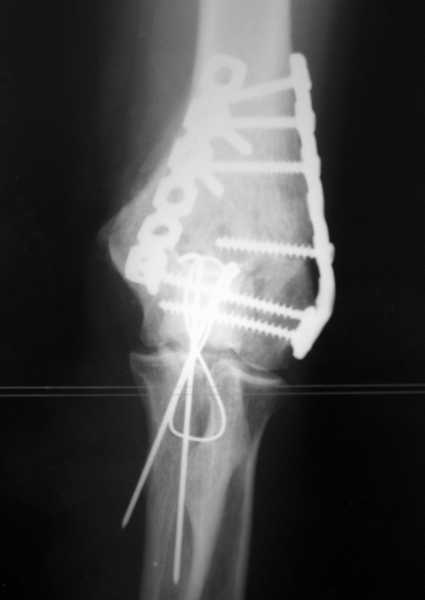

У пациентки 42 лет после операции остеосинтеза чрезмыщелкового перелома плеча, выполненной в нашей клинике 2 месяца назад, на контрольных R-граммах имеется гетеротопический оссификат по передней поверхности плеча.

Оперирована по методике АО, после операции максимально рано начала заниматся ЛФК. В настоящее время основная жалоба пациентки на ограничение сгибания в локтевом суставе. Клинически объем движений: сгибание 90 градусов, разгибание 170 градусов, ротационные движения в полном объеме. Привожу снимки сразу после операции и через 2 месяца. (На рентгенограммах после операции в мягких тканях по передней поверхности плеча имеется небольшой костный фрагмент, но его ширина во фронтальной плоскости не более 1 мм., обнаружен был по снимкам после операции. Интраоперационно основные крупные фрагменты отрепонировались хорошо, объем движений был сгибание до 75 градусов, разгибание 175 град.) Пациентка неудовлетворена объемом сгибания, хотя была предупреждена о высокой вероятности ограничения движений. Профилактика гетеротопической оссификации (прием индометацина) не проводилась, т.к. имелась язвенная болезнь, да и эффект от его приема считаю сомнительным.